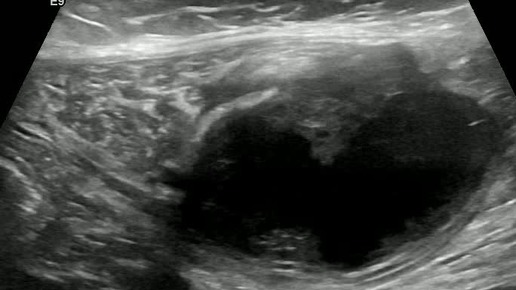

Видео к статье "Спонтанный разрыв прямой мышцы живота"https://dzen.ru/a/Z7_9JqiwzFHmuL7x

Ультразвуковые находки от врача УЗД Зорина Я.П.